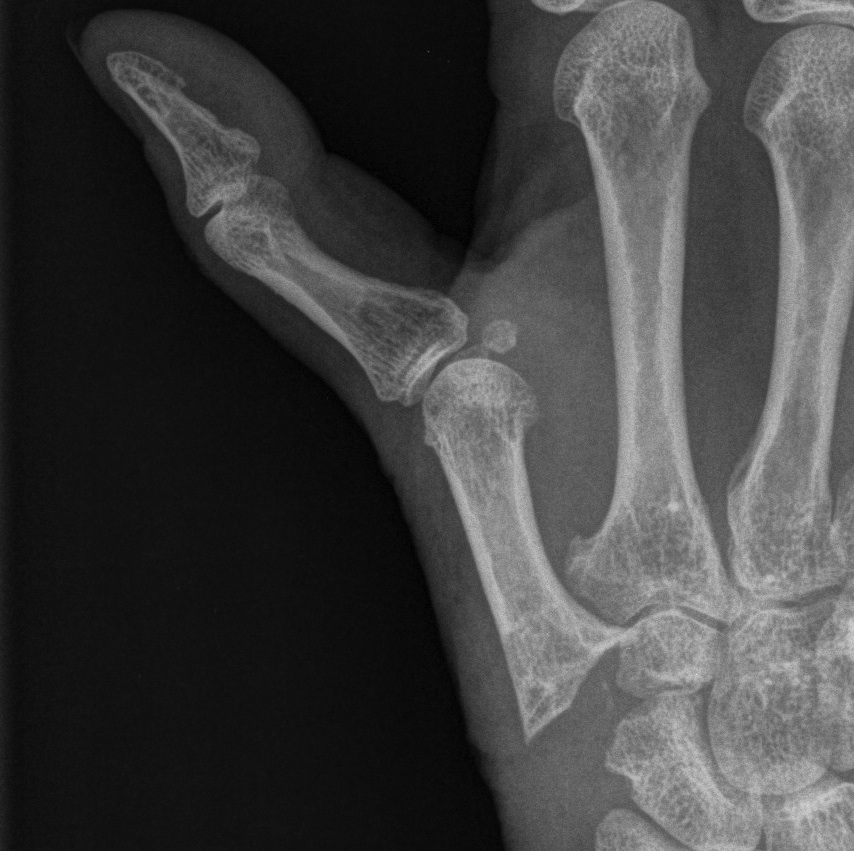

Type I - Boutonniere

- commonest

- MP flexion / IP hyperextension

- usually EPB rupture with EPL subluxation